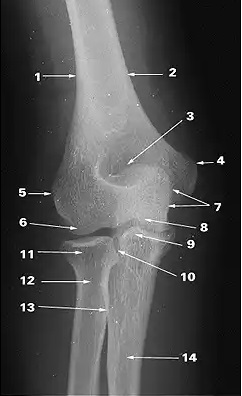

What does 1 indicate?

pisiform

What does 2 indicate?

triquetrum

medial supracondylar ridge

What does 3 indicate?

hook of hamate

What does 4 indicate?

capitate

What does 5 indicate?

scaphoid

What does 6 indicate?

trapezium

What does 7 indicate?

ulna

What does 8 indicate?

radius

olecranon

olecranon fossa

trochlea

What does 9 indicate?

coronoid process of ulna

medial epicondyle

lateral epicondyle

What does 10 indicate?

proximal radioulnar joint

capitulum